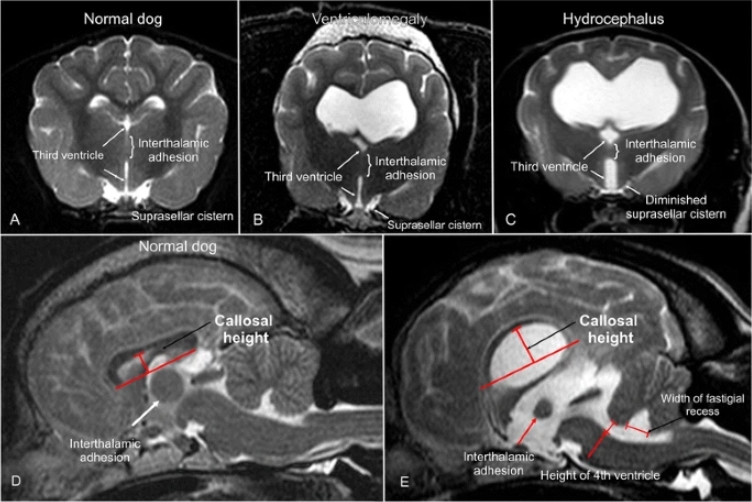

MRI สองสุนัขปกติ A ,D และผิดปกติ B , C , E

ตัวอย่างภาพ MRI สองสุนัขปกติ A ,D และผิดปกติ B , C , E จากบทความเผยแพร่ Magnetic resonance imaging signs of high intraventricular pressure – comparison of findings in dogs with clinically relevant internal hydrocephalus and asymptomatic dogs with ventriculomegaly

ที่มา https://bmcvetres.biomedcentral.com/articles/10.1186/s12917-015-0479-5